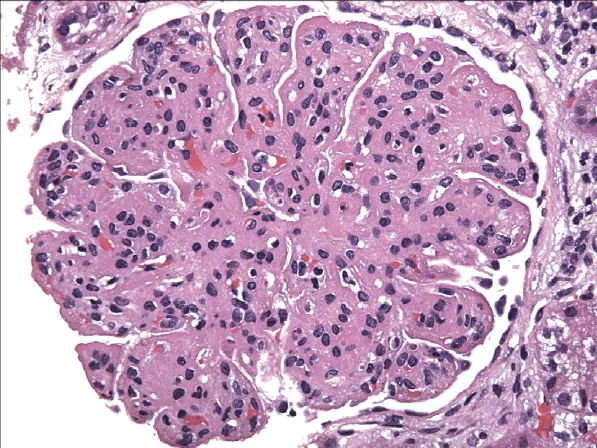

Meu paciente com NIgA tem proteinúria entre 0,5–1,0 g/dia, já está em iECA e iSGLT2: devo pensar em imunossupressão?

Proteinúria entre 0,5–1,0 g/dia na NIgA não é benigna e já se associa a maior risco de progressão renal. A evidência atual reforça <0,5 g/dia como alvo terapêutico, valorizando proteinúria cumulativa e tendência ao longo do tempo. Antes de pensar em imunossupressão, o foco deve ser otimização máxima da terapia de suporte e estratificação cuidadosa de risco.